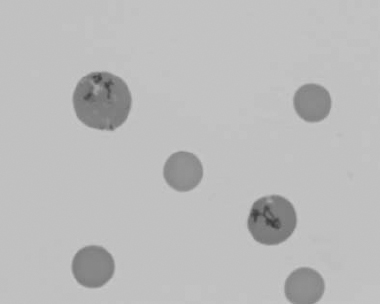

Figure 1.16 Feline blood film showing Mycoplasma hemofelis organisms (hemobartonellosis). Organisms are not always visible in blood smears from infected cats (also see color section).